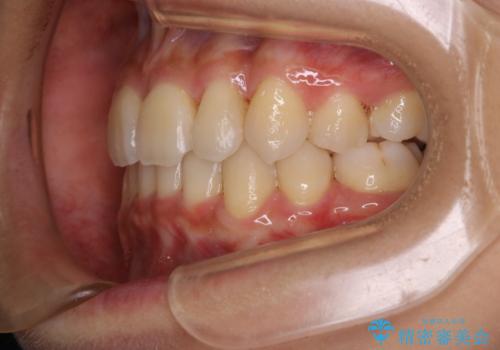

- 元々は海外でワイヤー矯正を行っていたが、コロナ禍で海外への往来が難しくなり、治療を中断せざるを得なくなってしまった方です。

ご本人のご希望により、インビザラインによる治療を行いました。

ブラケット除去直後に目立っていた下顎前歯部の大きなブラックトライアングルもあまり目立たなくなり、大変喜んでいただけました。